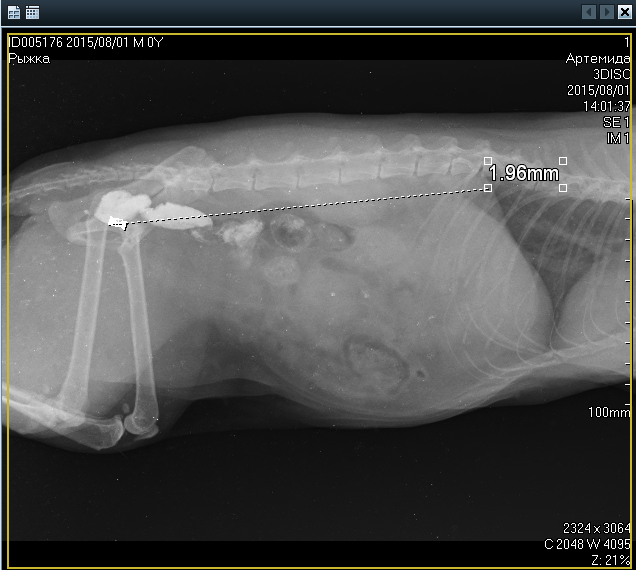

Рентген:

Вложения

1.jpg

2.png

рыжка 1.png

рыжка 2.png

Самое главное, после позавчерашнего рентгена с контрастом она не ходила по-большому. Где -то у нее этот сульфат бария сидит, меня это очень настораживает, когда делали рентген, врач сказала, что до толстого кишечника контраст еще не дошел, может у нас в нем проблемы?

4 часа просидели в очереди!!! Были на приеме у 8-го по счету врача, сделали еще раз рентген. Врач сказал:

1. В толстом кишечнике вроде тоже все нормально.

2. Что не было стула - там все на подходе, контрастное вещество может вызвать запор, это обычное, в случае правильной работы кишечника, явление.

3. Очень долго рассматривал все наши 3 снимка и однозначно сказал, что на всех снимках в каловых массах очень много шерсти (Рыжка на самом деле очень чистоплотная кошка, постоянно вылизывается). Эта невыходящая шерсть может прилипать к стенкам желудка и кишечника и образовывать воспаления и язвочки.

4. Еще ему не понравилось состояние десен (они на самом деле воспаленные (красные)), поставил нам возраст 7-8 лет, что в 2-3 раза превышает предыдущий поставленный возраст (это минимум), и оказывается у нас нет нескольких зубов (на самом деле нет передних резцов и одного клыка! ). Клык я и раньше не видела, а про резцы - первый раз! (Куда смотрели предыдущие 7 врачей?! )